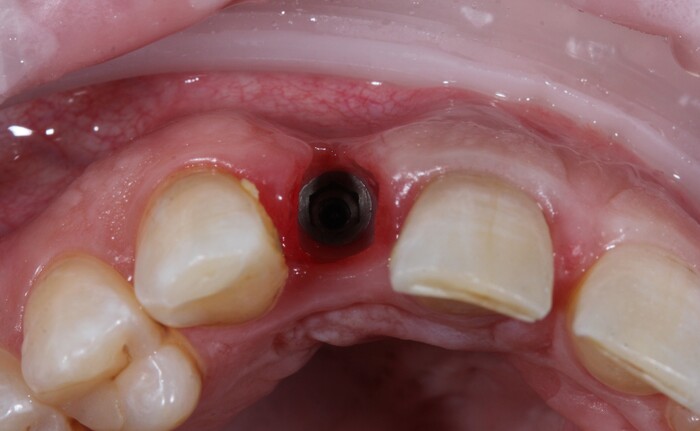

Но мне повезло, ко мне на прием пришла прекрасная девушка (а не усатый господин в плаще на голое тело) с ужасной, с ее слов, проблемой. Когда-то давно ей поставили имплантат в области верхнего бокового резца, но в связи с тем, что положение имплантата было неправильным, а одномоментно с имплантацией пластики десны не проводилось, последняя начала постепенно «подниматься», оголился абатмент (та часть, «за которую держится коронка»). Со слов пациентки, тем же доктором была предпринята попытка сделать пластику десны, не снимая этой коронки. Но, увы, развился некроз, что только усугубило ситуацию.

На момент моего осмотра это выглядело так:

Согласитесь, не особо эстетично. Ортопантомограмма: